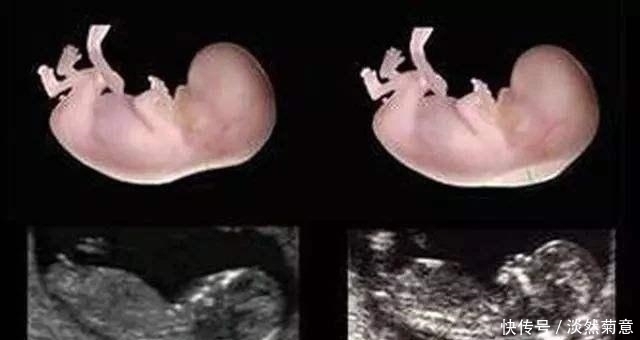

怀孕6-8周,做B超看胎儿是否已经出现 胎心胎芽,这个孕周大多可以看出来了。

只有检查 胎儿在正常发育,已经看到了胎心搏动,孕妈就可以放心了,等到怀孕12周再去检查。